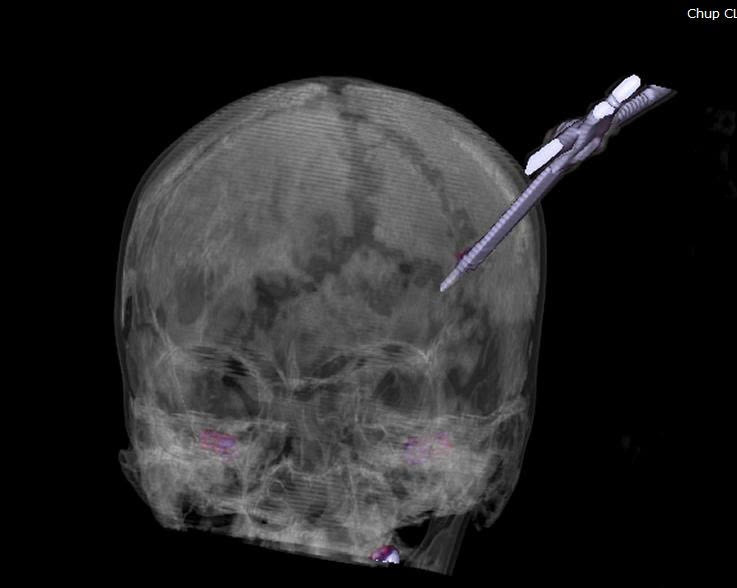

Nhận định đây là một ca chấn thương sọ não phức tạp, người bệnh được chụp cắt lớp vi tính sọ não để đánh giá chính xác vị trí tổn thương và mức độ đâm xuyên của dị vật, từ đó có đường mổ an toàn, hạn chế tổn thương tối đa tổn thương não, tránh biến chứng nặng.

Hình ảnh kéo sắc nhọn đâm xuyên não - Ảnh BVCC

Dưới sự chỉ đạo trực tiếp của BS.CKII Nguyễn Tiến Dũng, Phó Giám đốc Bệnh viện, kíp mổ hội chẩn với các chuyên khoa đánh giá đây là vết thương xuyên sọ sâu khoảng 5 cm xâm lấn nhu mô não, nguy cơ chảy máu sâu bên trong não kèm nguy cơ nhiễm trùng lan rộng do dị vật găm xuyên sọ, vì vậy bệnh nhân lập tức được chuyển phòng mổ cấp cứu lấy dị vật, xử trí tổn thương não cho người bệnh.

Ngay trong tối cùng ngày, kíp mổ cấp cứu khoa Phẫu thuật Thần kinh – Cột sống phối hợp với khoa Gây mê Hồi sức thực hiện. Qua phim chụp, các bác sĩ đánh giá dị vật không xâm lấn vào mạch máu lớn.

Hình ảnh chụp cắt lớp dị vật sắc nhọn đâm xuyên não - Ảnh BVCC